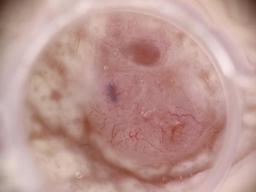

MILK10k consists of 10480 images, each representing a paired clinical close-up and dermatoscopic image for 5240 lesions. The dataset’s metadata include age (in 5-year intervals), sex, anatomic site, skin tone, diagnosis, method of ground truth establishment (histopathology or other means), and, if a dermatoscopic image of the same lesion was previously included in ISIC, its corresponding ISIC identifier. Skin tone is categorized into six levels, ranging from very dark (0) to very light (5), intentionally distinct from the Fitzpatrick skin types to avoid confusion. Most patients had skin tones in the middle ranges. Of the 5240 lesions, 95.7% were biopsied or excised, with histopathology serving as the gold standard for diagnosis. Diagnoses were mapped to both the ISIC-Dx diagnostic scheme and a simplified classification based on the ISIC2018/2019 challenge and HAM10000 diagnostic categories. The dataset includes 11 broad diagnostic categories:

Additionally, we provide the most specific ISIC-Dx diagnosis and its parent branch in the ISIC-Dx diagnostic tree. In cases where a dermatoscopic image of the same lesion was already included in the ISIC archive, its ISIC identifier is reported in the metadata. Furthermore, all images have been annotated using the MONET framework, with probabilities for the following concept term groups included in the metadata: